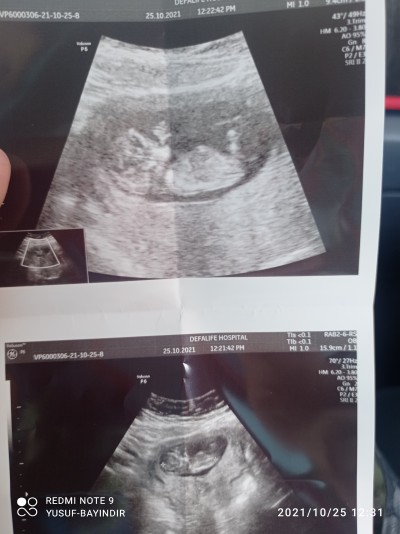

12 haftalık gebeyim doktor küçük diye söylemedi merek ediyorum 3 kızım var hakkımızda hayırlısı olsun

Gebelik haftası 12